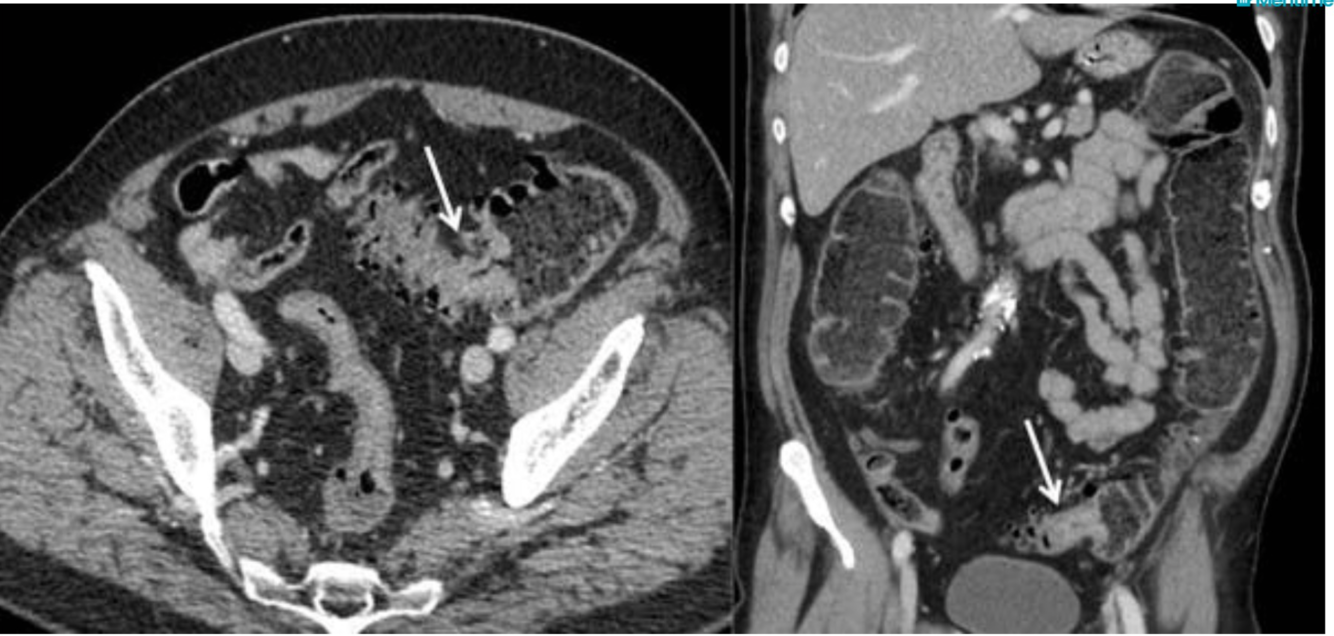

what does this image show?

Large bowel bostruction at arrows with dialtation proximal to site of obstruction

what are the causes of bowel obstruction?

Small bowel: adhesions and hernia

Large: cancer, diverticular and volvulus

Can also seperate into Intraluminal, mural and extramural